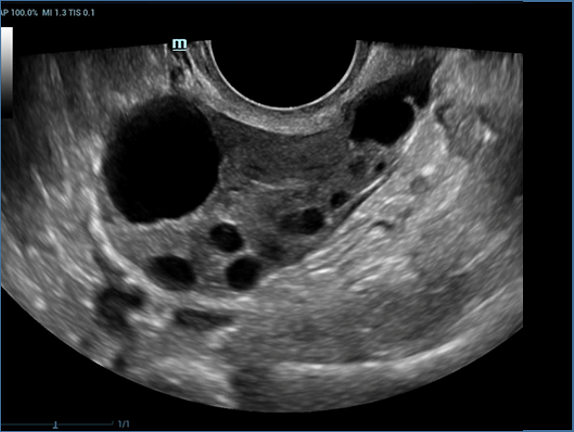

Mindray, ?irketin kuruldu?u gĂŒnden bu yana sĂŒrekli olarak tan?sal do?rulu?u iyile?tirmeye ?al??maktad?r. Devrim niteli?indeki ZONE Sonography? Teknolojisi ile desteklenen Resona 7ânin yeni ZST+ platformu, b?lge g?rĂŒntĂŒsĂŒ alma ve kanal veri i?leme ?zellikleri ile ultrason g?rĂŒntĂŒsĂŒ kalitesini daha ĂŒst bir dĂŒzeye ??kar?yor.

Resona 7, ĂŒstĂŒn dĂŒzeyde g?rĂŒntĂŒ kalitesine ek olarak, vaskĂŒler hemodinamik de?erlendirmesi i?in devrim niteli?indeki V Ak??? ile fetĂŒs CNS tan?lamas? i?in 3 boyutlu veri kĂŒmesinden dĂŒzlem g?rĂŒntĂŒsĂŒ alma konusunda en iyi birime sahip oldu?undan, klinik ara?t?rma yeterliklerini de art?rmaktad?r. En sezgisel, harekete dayal? ?oklu dokunmatik i?letim ile tĂŒm temel klinik ?zellikleri bir araya getiren Resona 7, ultrason yenili?i konusunda ger?ek anlamda yeni dalgalara ?ncĂŒlĂŒk ediyor.